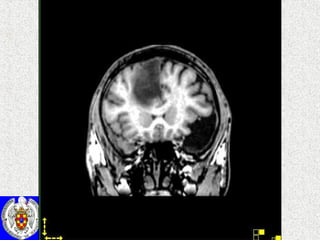

Resonancia Magnética (RM) Creación de un campo magnético y se recoge la actividad de los núcleos de hidrógeno. Detecta la energía liberada por los núcleos de hidrógenos cuando el orden y el movimiento son interrumpidos por impulsos de radiofrecuencia

Resonancia Magnética (RM)

Resonancia Magnética (RM)Creación de un campo magnético y se recoge la actividad de los núcleos de hidrógeno. Detecta la energía liberada por los núcleos de hidrógenos cuando el orden y el movimiento son interrumpidos por impulsos de radiofrecuencia